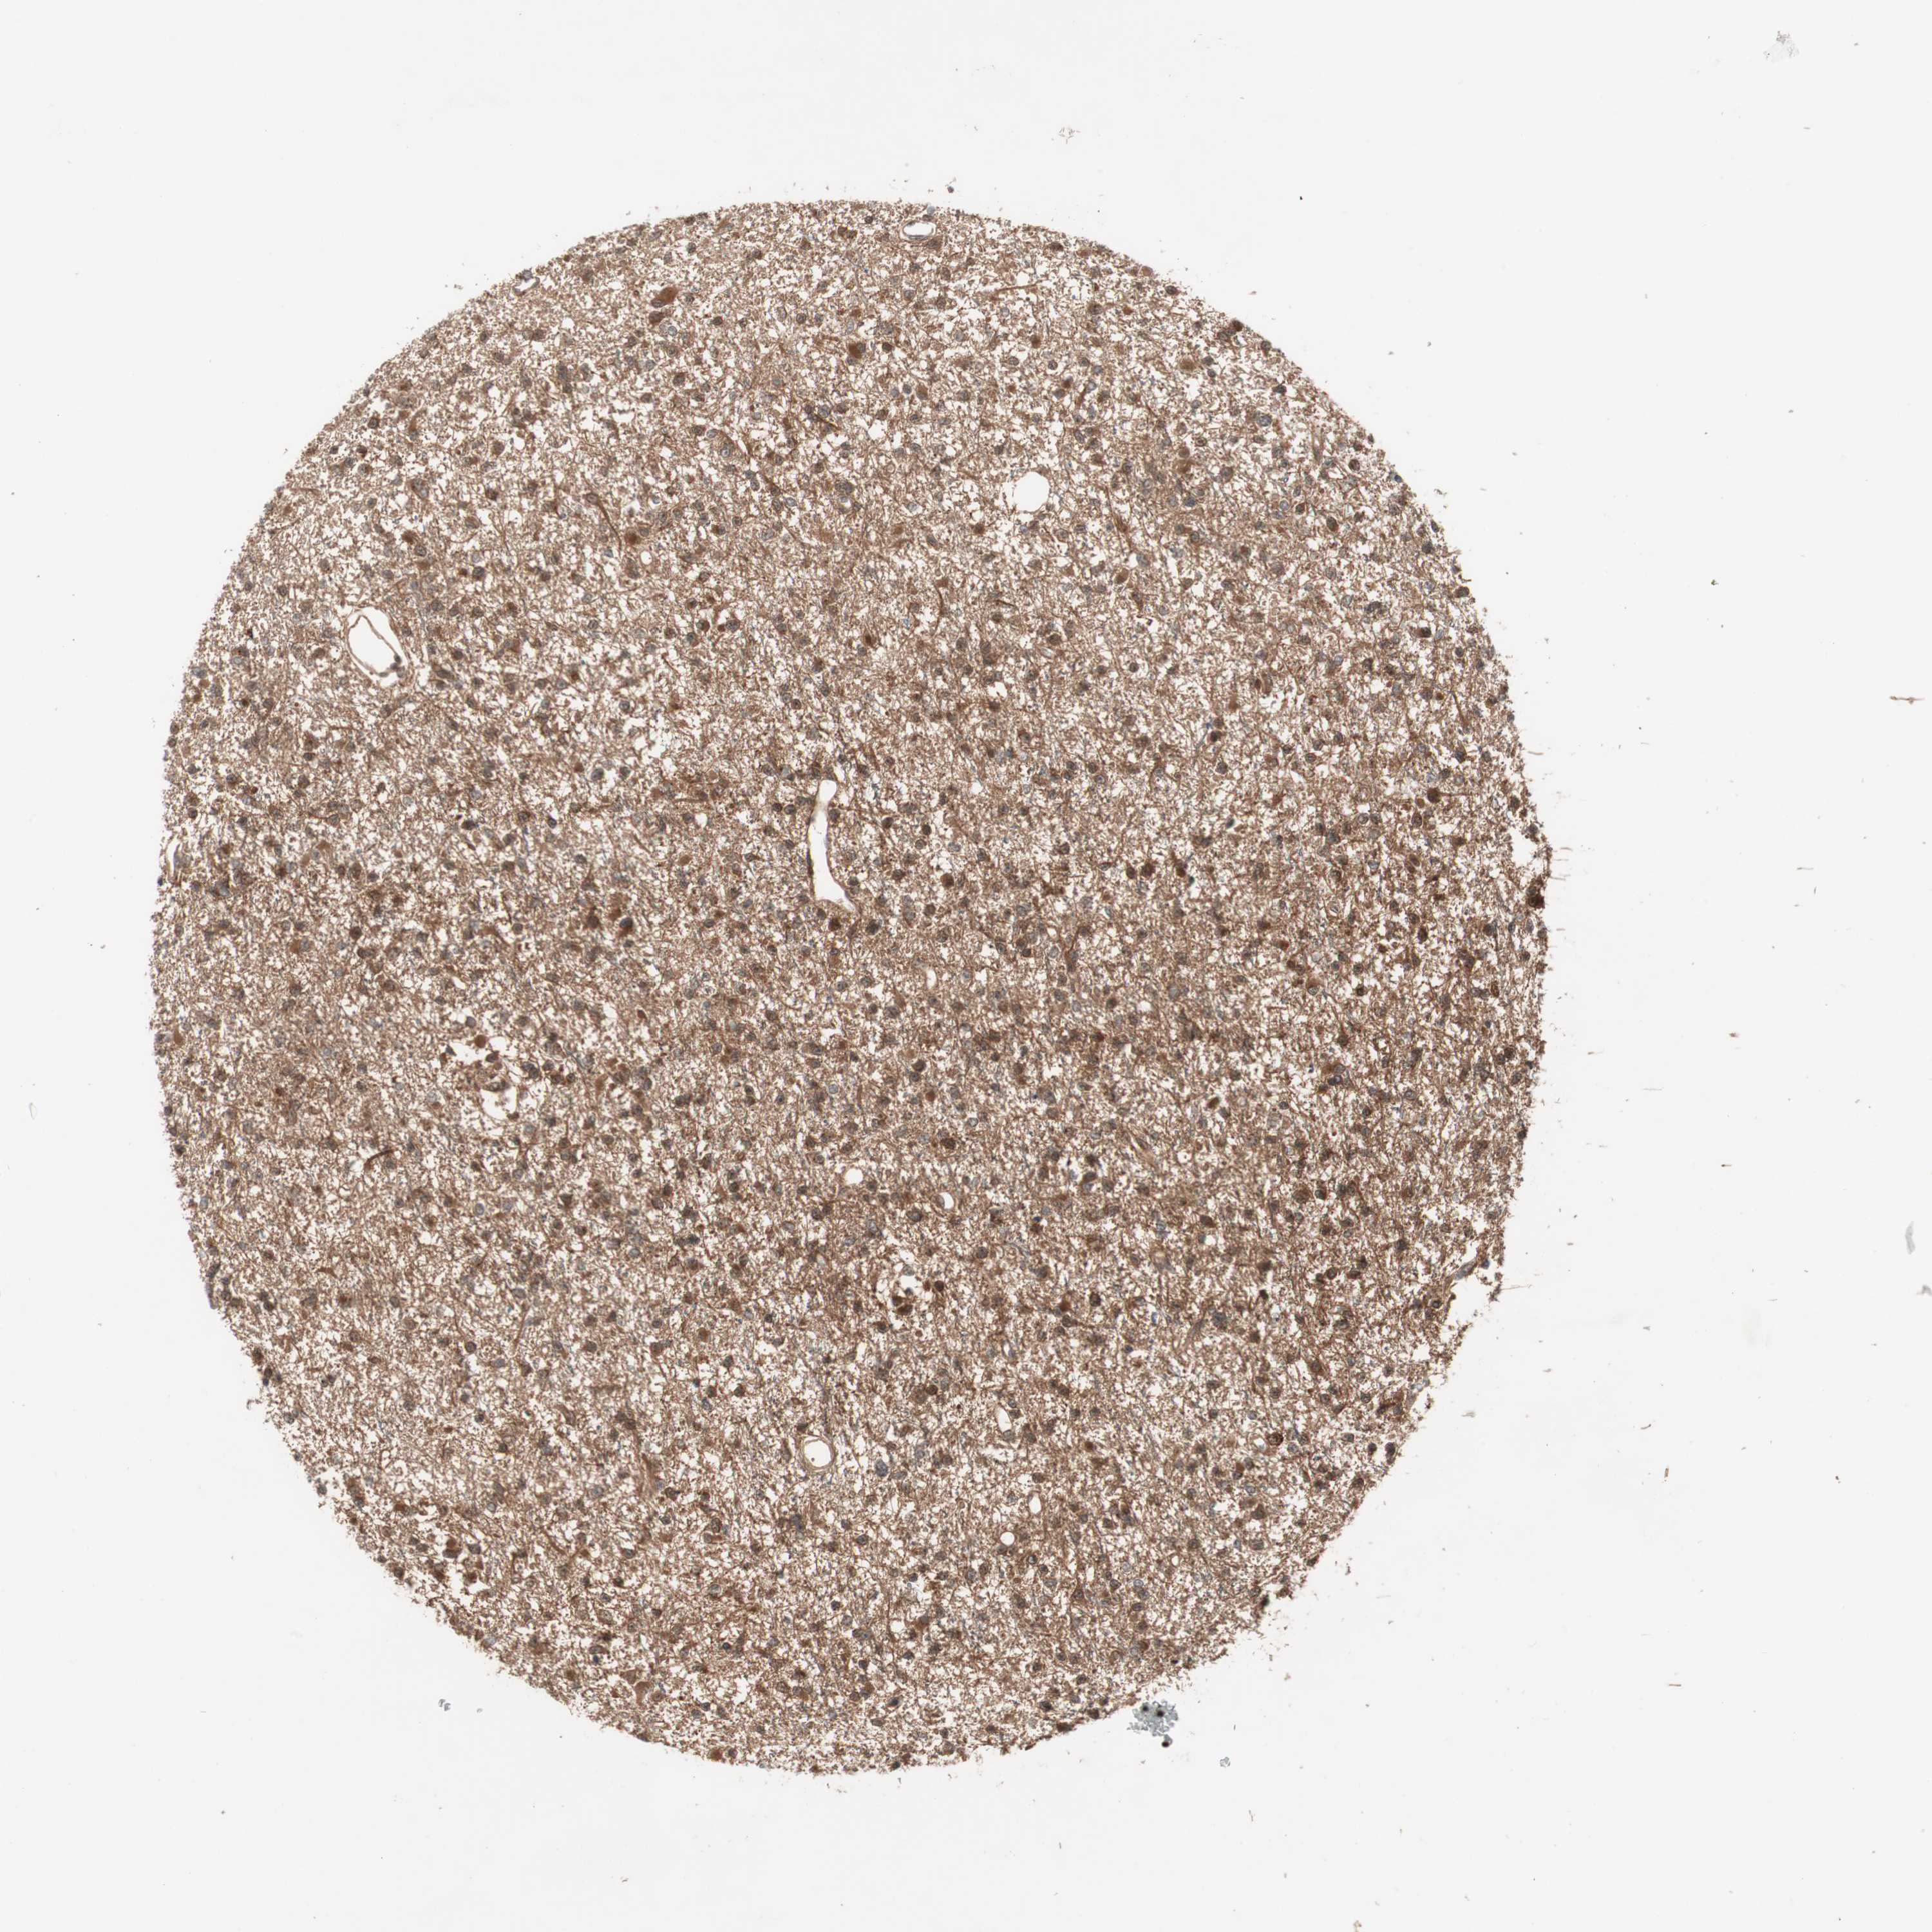

GLIOMA - Protein expressioni

A mouse-over function shows sample information and annotation data. Click on an image to view it in a full screen mode. Samples can be filtered based on level of antibody staining by selecting one or several of the following categories: high, medium, low and not detected. The assay and annotation is described here.

Note that samples used for immunohistochemistry by the Human Protein Atlas do not correspond to samples in the TCGA dataset.

Antibody stainingi

Antibody staining in the annotated cell types in the current human tissue is reported as not detected, low, medium, or high, based on conventional immunohistochemistry profiling in selected tissues. This score is based on the combination of the staining intensity and fraction of stained cells.

Each image is clickable and will lead to virtual microscopy that enables deeper exploration of all samples and also displays staining intensity scores, fraction scores and subcellular localization as well as patient and tissue information for each sample.

Antibody HPA007386

Antibody CAB018739

Glioma, malignant, Low grade

Glioma, malignant, High grade